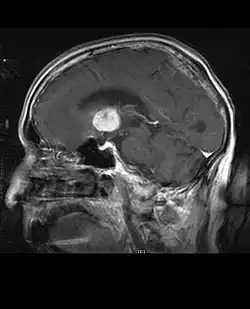

Na -MRI ukazuje intrakraniální tumor jako masivní lézi, která se po použití kontrastní látky může stát více luminiscenční. Vždy však dojde k anomálii signálu -Magnetická rezonance, která indikuje přítomnost neoplazie nebo vazogenního edému. Obvykle zvýšená luminiscence (zesílení kontrastu) svědčí pro nádor vyššího stupně malignity. Pro glioblastom je charakteristický kontrastní prstenec, jehož luminiscenční část odpovídá vitální části maligního nádoru a tmavší -hypointense oblast odpovídající nekróze tkáně.

Typicky se u pacientů s anaplastickým astrocytomem objevují epileptické záchvaty, fokální neurologické deficity, bolesti hlavy a změny osobnosti. Průměrný věk pacientů je 45 let. Magnetická rezonance obecně ukazuje masivní lézi se zvýšeným kontrastním signálem, který může být i slabší. Diagnóza je histologickým vyšetřením léze biopsií nebo chirurgickou resekcí.

Horší prognóza může být spojena s pokročilým věkem, špatnou fyzickou kondicí a významným neurologickým poškozením. Obecně platí, že léčebný výsledek je lepší při kompletní chirurgické resekci (standardní léčbě) bez zvýšení neurologického deficitu. Radiační terapie je standardní, protože bylo prokázáno, že prodlužuje dobu přežití. Role chemoterapie je kontroverzní.